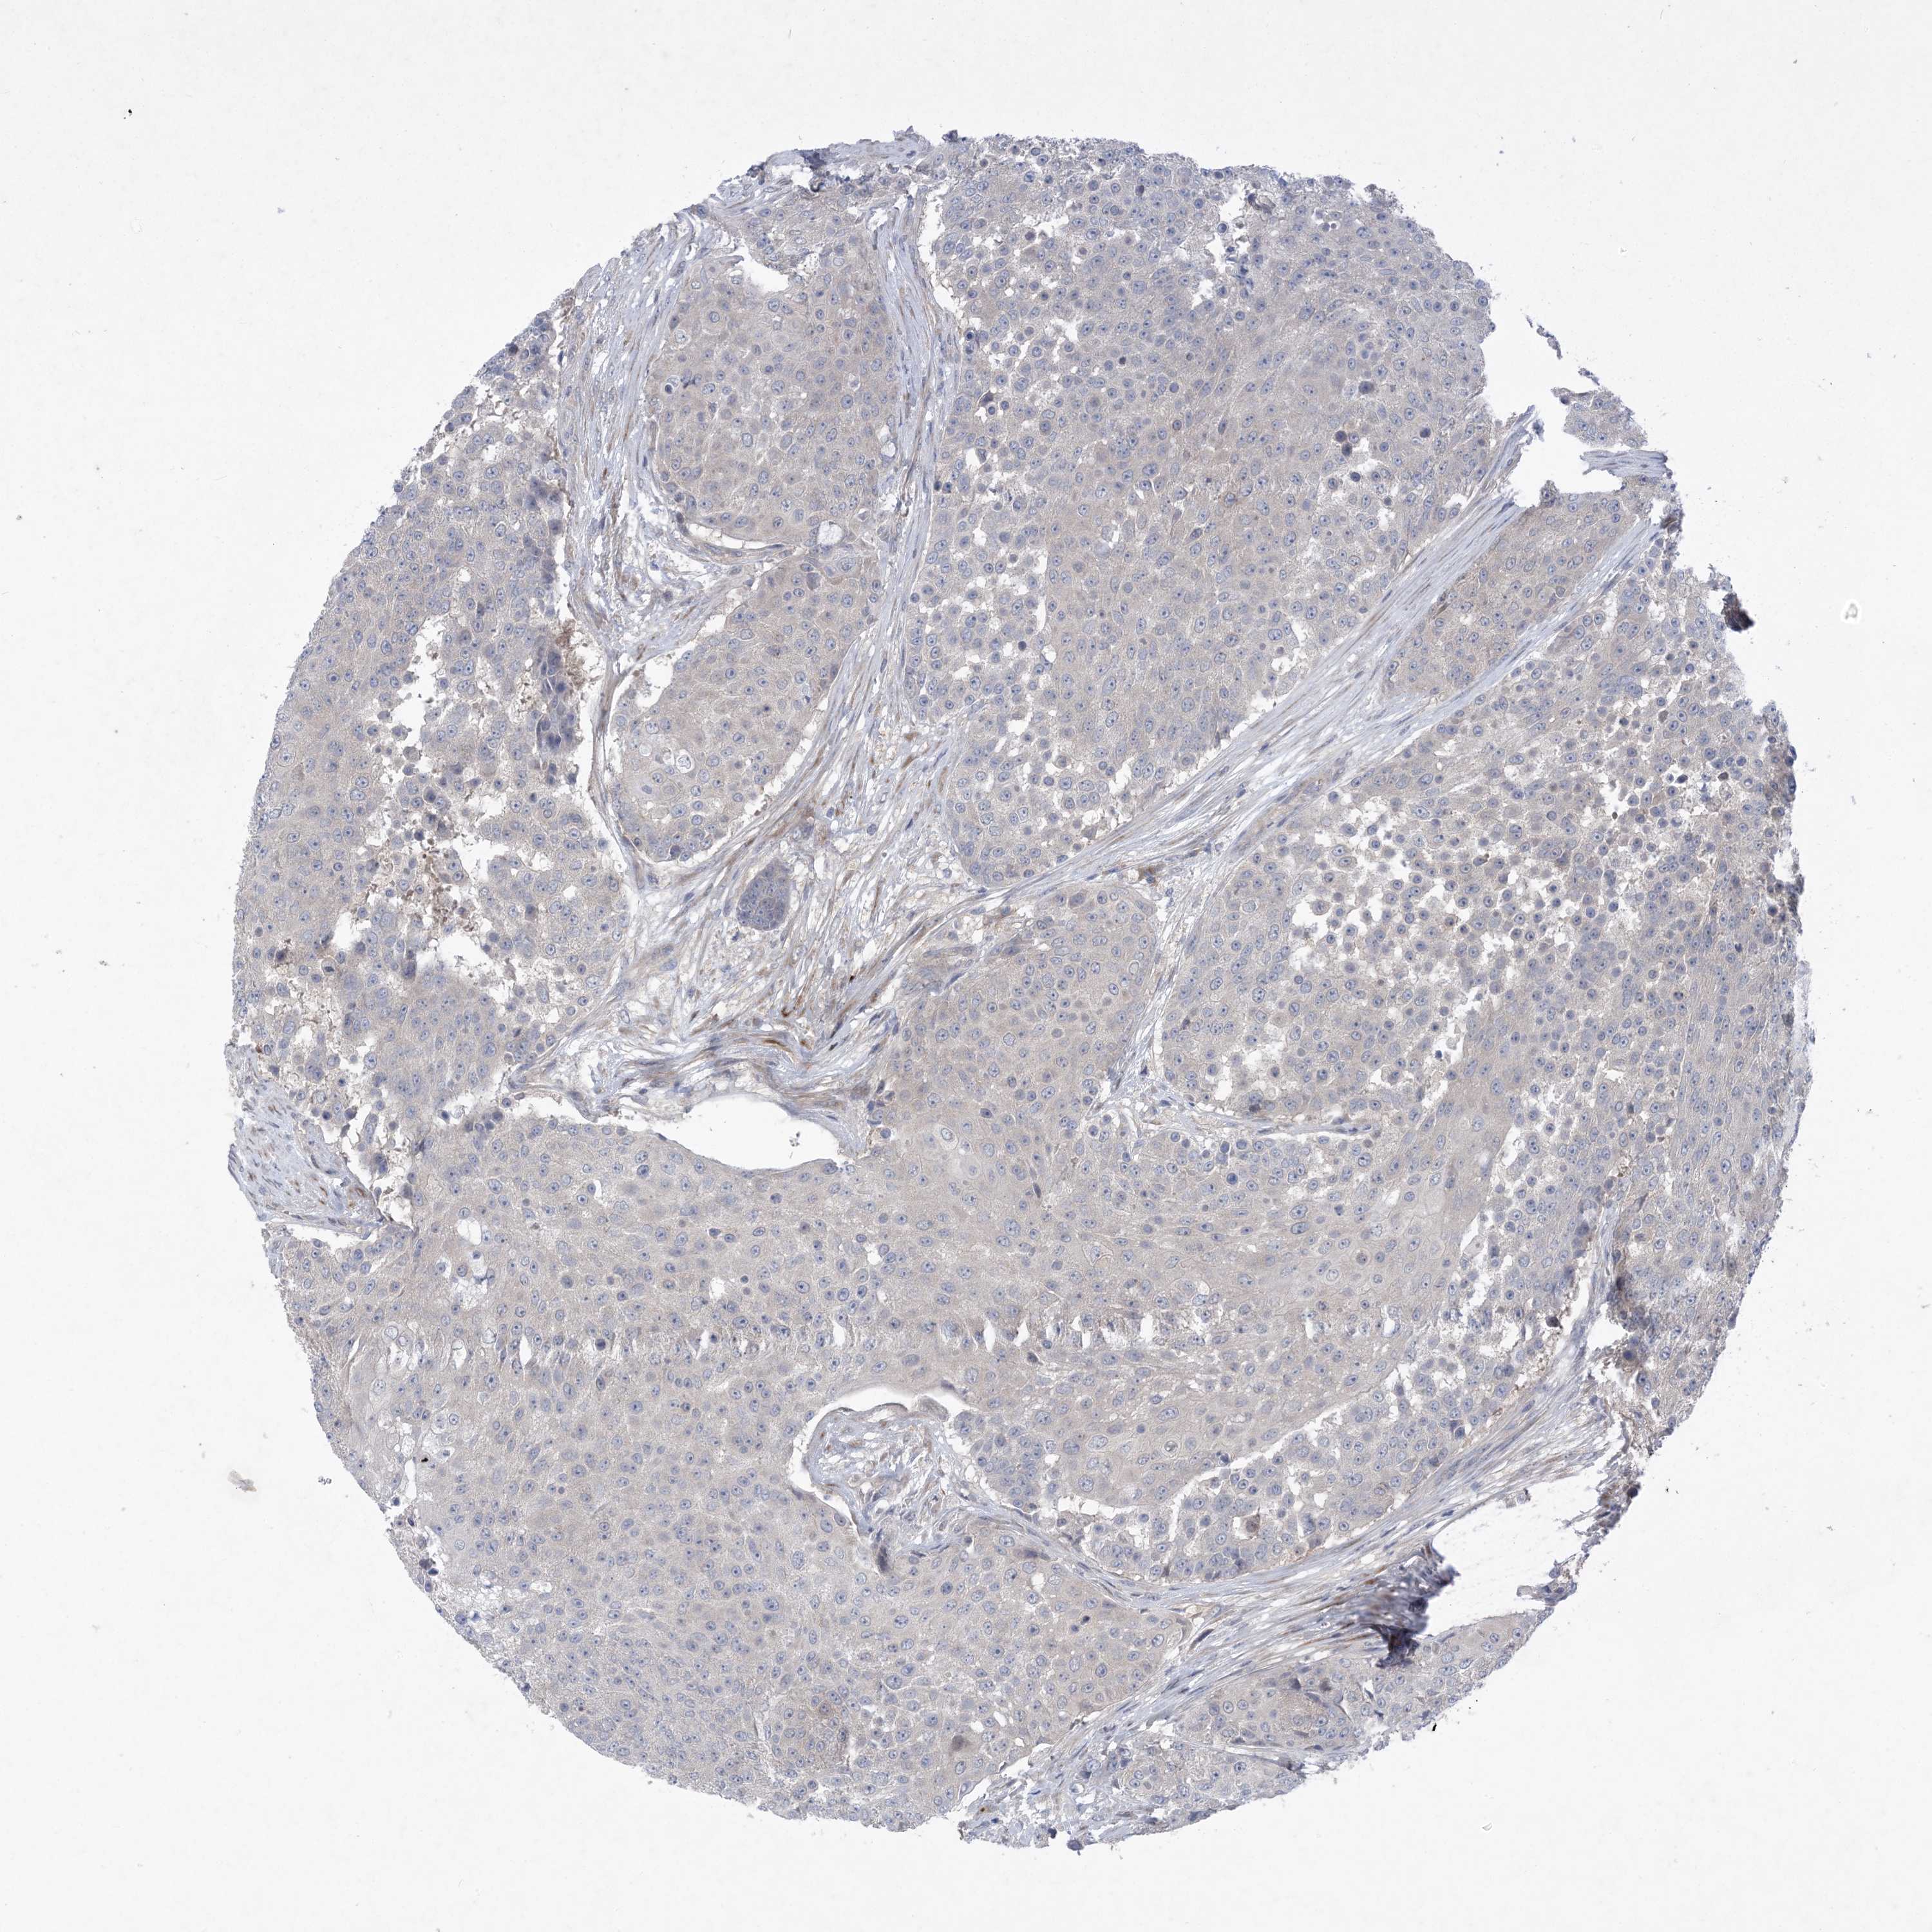

UROTHELIAL CANCER - Protein expressioni

A mouse-over function shows sample information and annotation data. Click on an image to view it in a full screen mode. Samples can be filtered based on level of antibody staining by selecting one or several of the following categories: high, medium, low and not detected. The assay and annotation is described here.

Note that samples used for immunohistochemistry by the Human Protein Atlas do not correspond to samples in the TCGA dataset.

Antibody stainingi

Antibody staining in the annotated cell types in the current human tissue is reported as not detected, low, medium, or high, based on conventional immunohistochemistry profiling in selected tissues. This score is based on the combination of the staining intensity and fraction of stained cells.

Each image is clickable and will lead to virtual microscopy that enables deeper exploration of all samples and also displays staining intensity scores, fraction scores and subcellular localization as well as patient and tissue information for each sample.

Antibody HPA035063

Antibody HPA035064

Staining

High

Medium

Low

Not detected

Intensity

Strong

Moderate

Weak

Negative

Quantity

>75%

75%-25%

<25%

None

Location

Nuclear

Cytoplasmic/membranous

Cytoplasmic/membranous,nuclear

Urothelial carcinoma, High grade

Urothelial carcinoma, Low grade